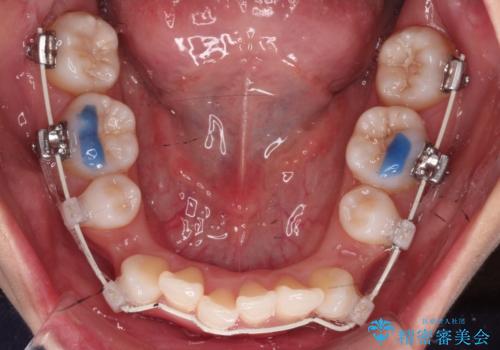

- 矯正装置

- 審美装置

凸凹を治すために、上下左右の小臼歯を抜歯してワイヤー矯正を行いました。

患者様には、顎間ゴムを使用していただくことで、2年という期間で治療を終了することができました。